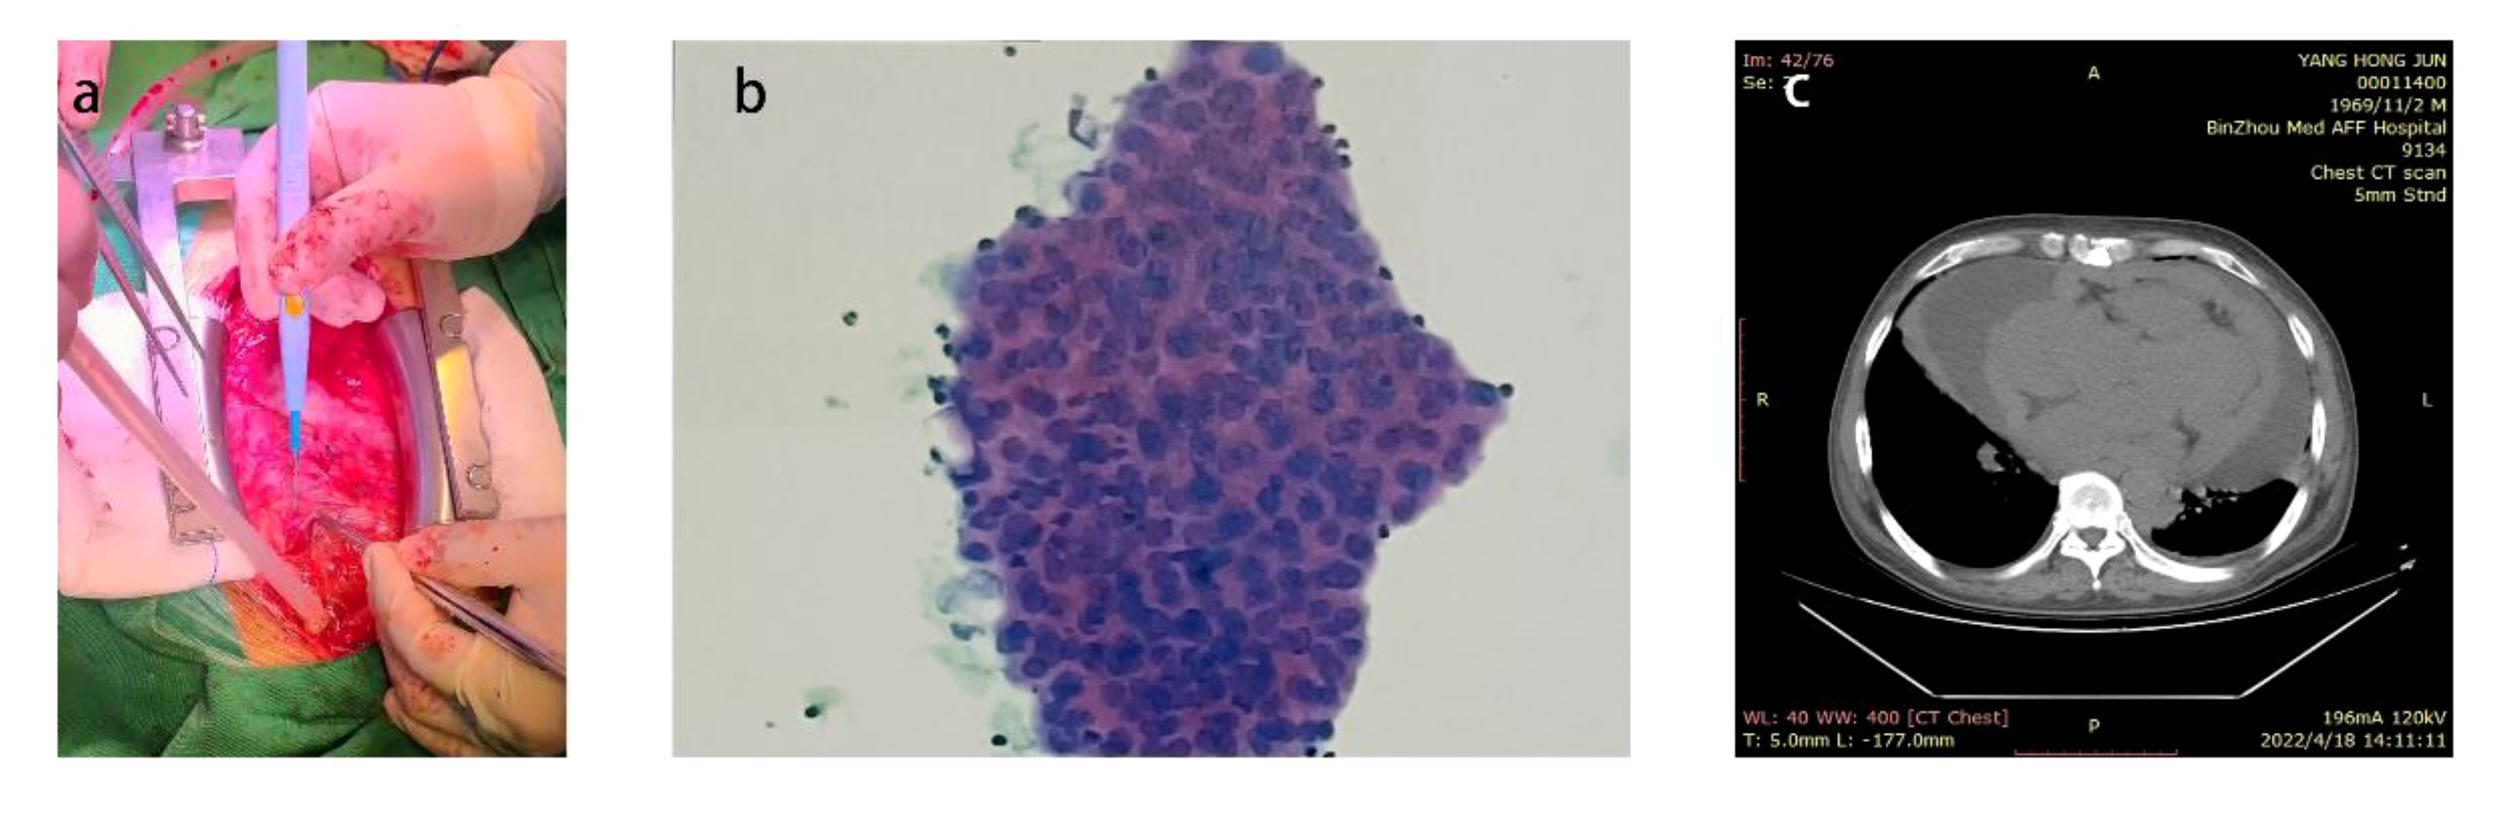

Figure 1

(A) The patient presented with a significant volume of pericardial effusion within the pericardial cavity. (B) Pathological results of pericardial effusion (C) Preoperative chest CT prompted a large number of pericardial effusion.